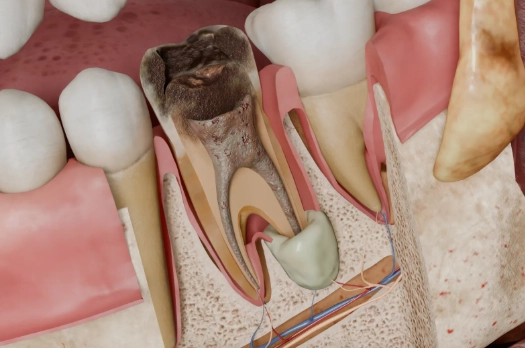

Think of your tooth like a house. The hard enamel is the exterior walls. Inside, there's a living space called the pulp chamber, which contains nerves, blood vessels, and connective tissue. This chamber has a long basement that extends down each root—the root canal. When bacteria break through the walls (from a deep cavity or crack), they invade this living space.

The body fights back, sending immune cells. That fight creates pus—a mix of dead tissue, bacteria, and white blood cells. As pressure builds in the confined root canal space, the infection is forced out the tiny opening at the root's tip (the apex), into the jawbone. That's your periapical abscess. "Periapical" literally means "around the apex."

The gold standard is the dental X-ray. A periapical radiograph shows the bone around the root tips. A healthy root is surrounded by a thin, uniform black line (the periodontal ligament space). An abscess shows up as a dark, circular shadow at the root's tip—that's the bone loss caused by the infection. Sometimes, in early stages, it won't show on an X-ray. In those cases, a more detailed 3D cone beam CT scan might be needed to see the extent of bone destruction.